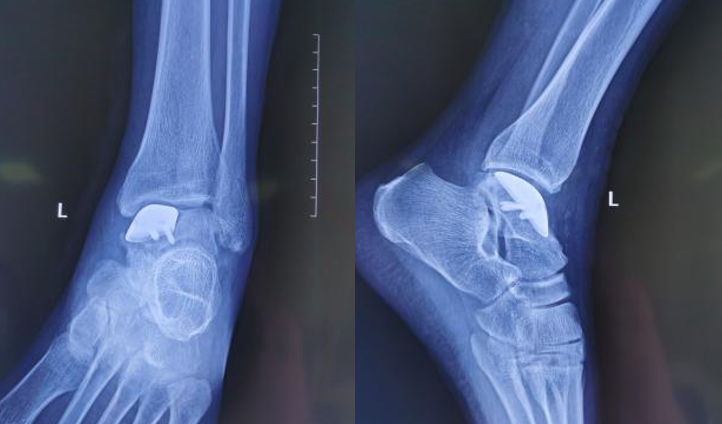

术后X线情况